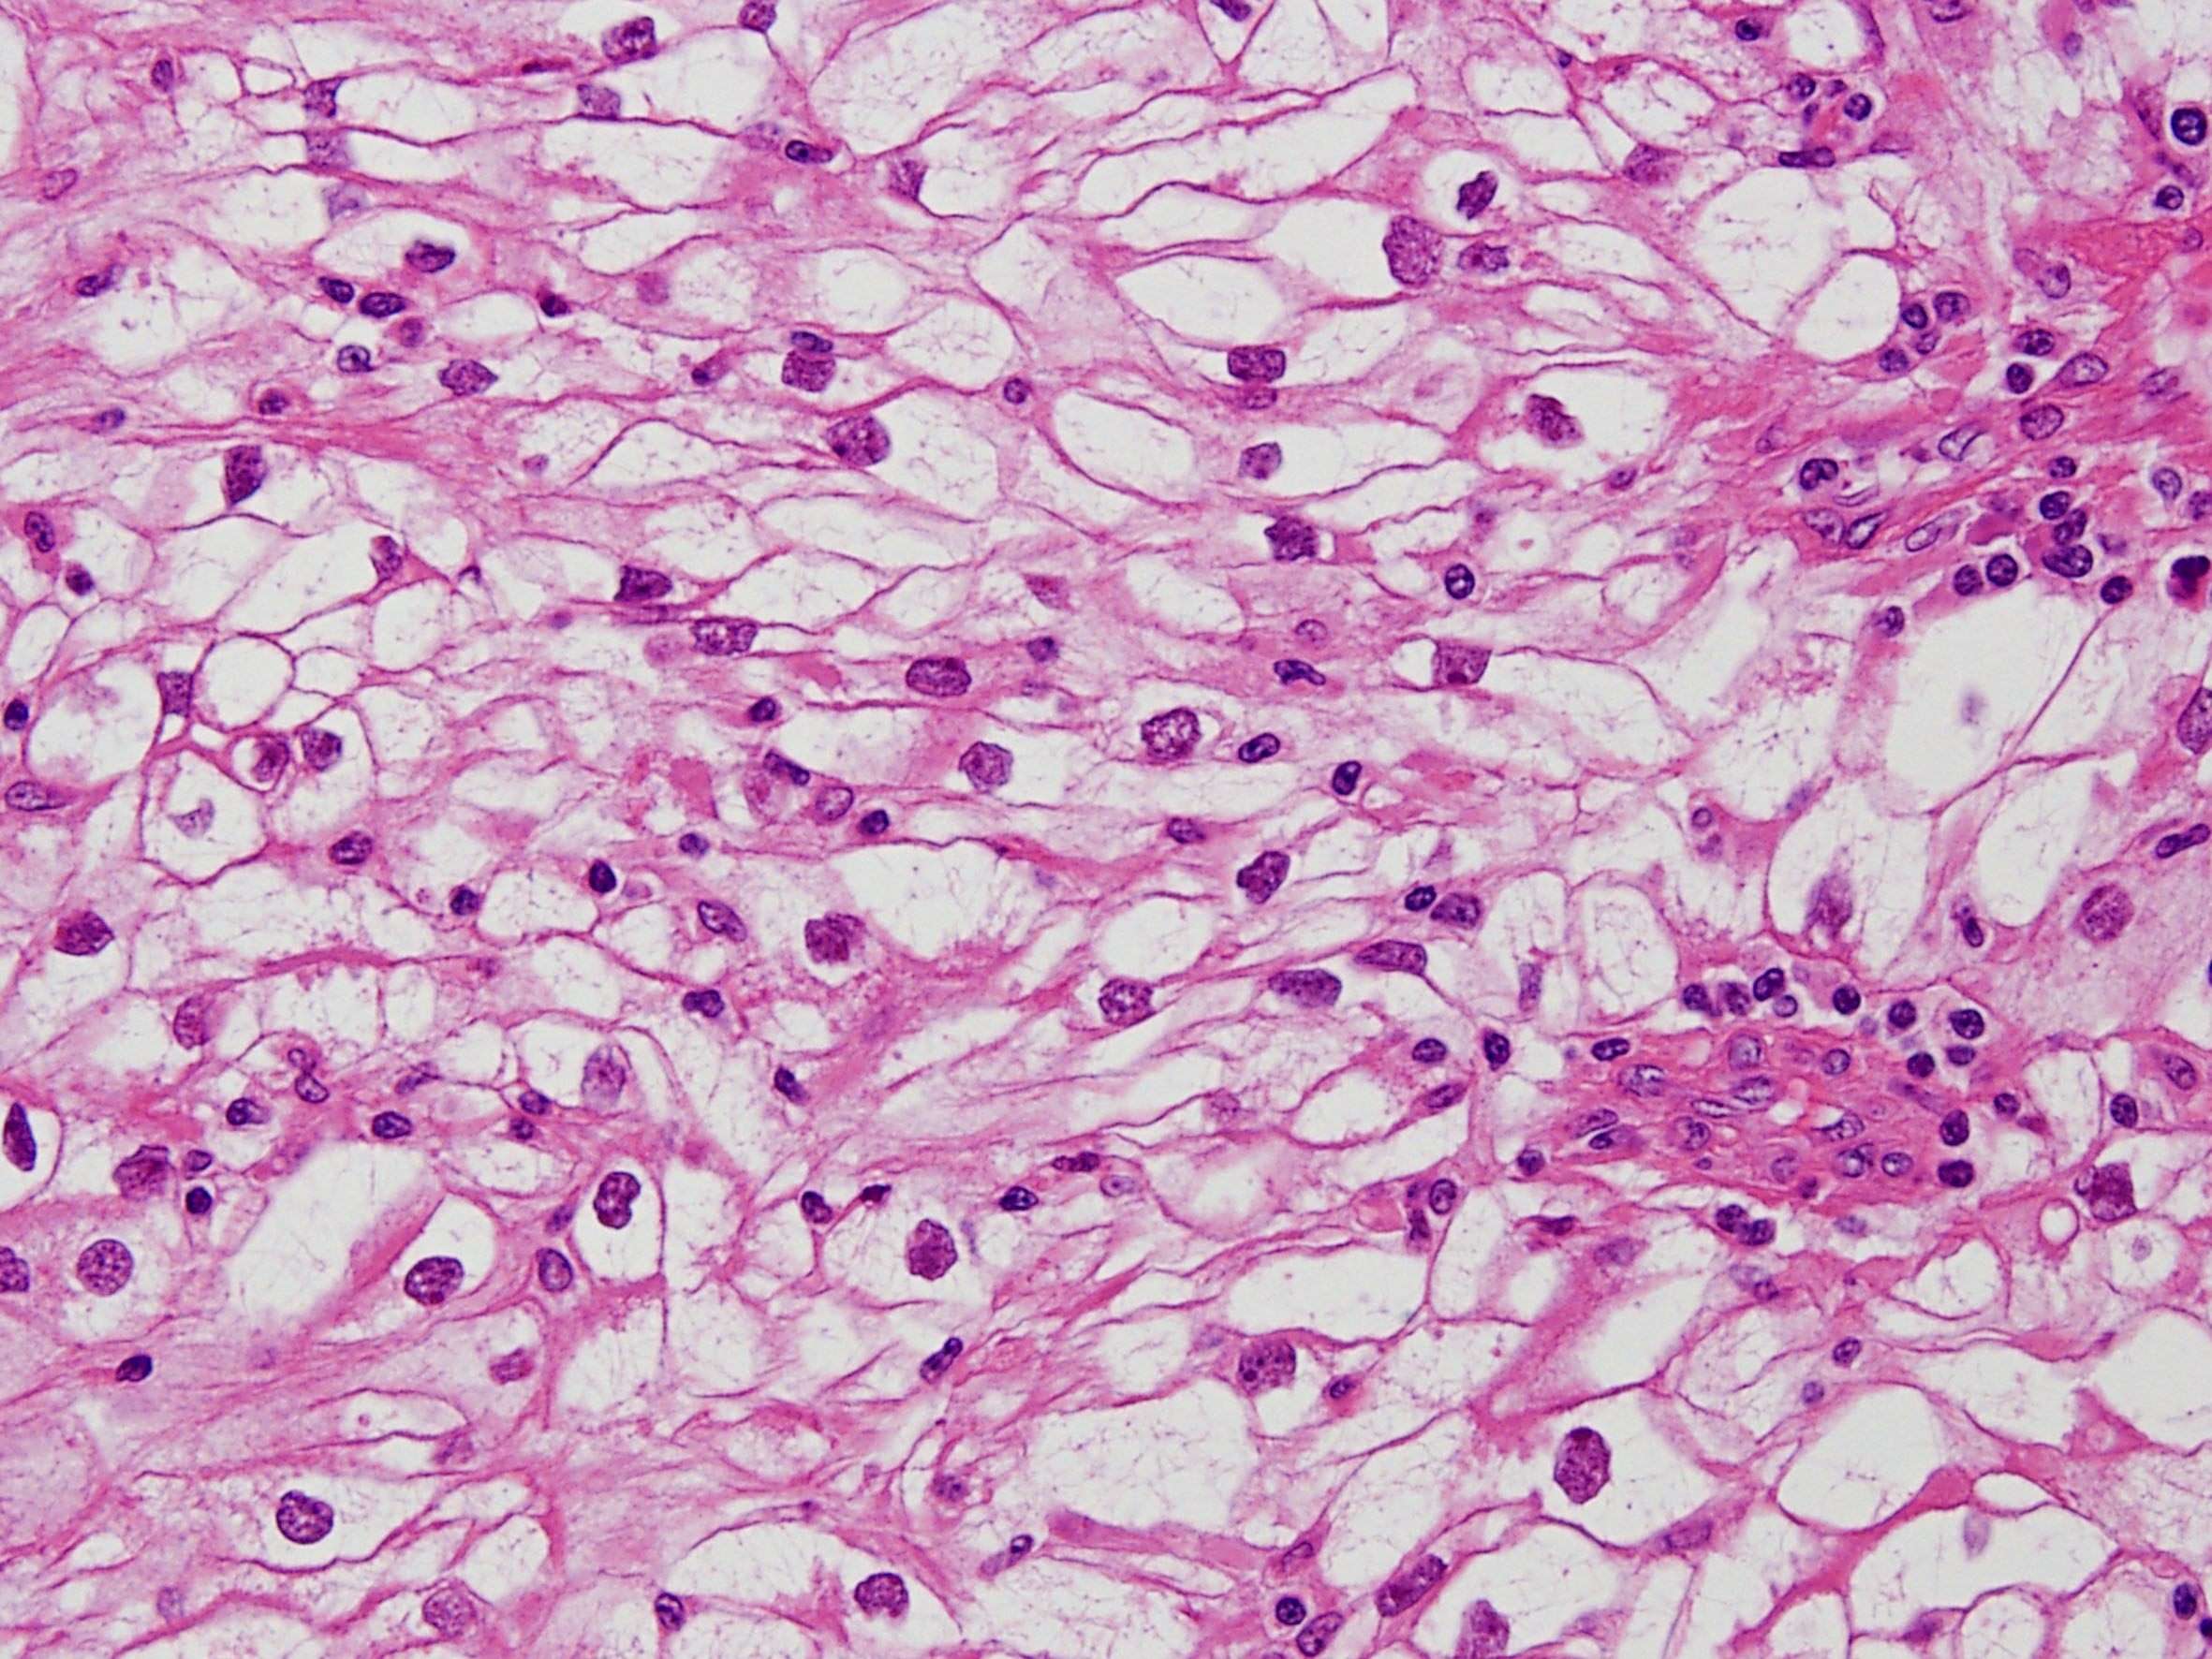

Classification of renal tumors

Case ID: 258